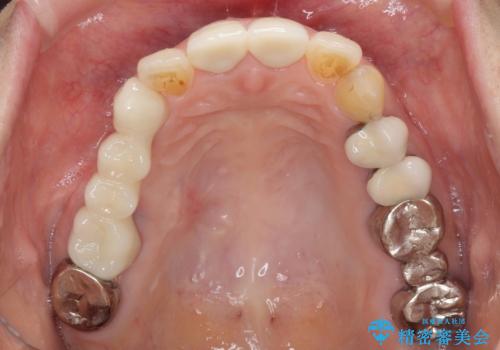

前歯2本を同時に処置したことにより、色合いも形態もバランスの取れた仕上がりとすることができました。

10年近く人にあまり見られないようにしていた前歯でしたが、人目を気にせず笑えるようになり、患者様には大変満足していただきました。